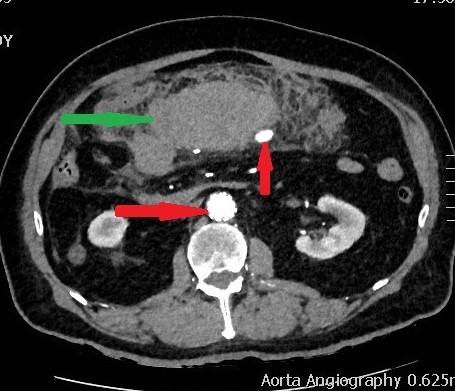

CT κοιλίας. Μεταστατικές εστίες στους σκελετικούς μύες δεξιά (κόκκινα βέλη) (Ευγενική παραχώρηση Dr. V. Penopoulos)